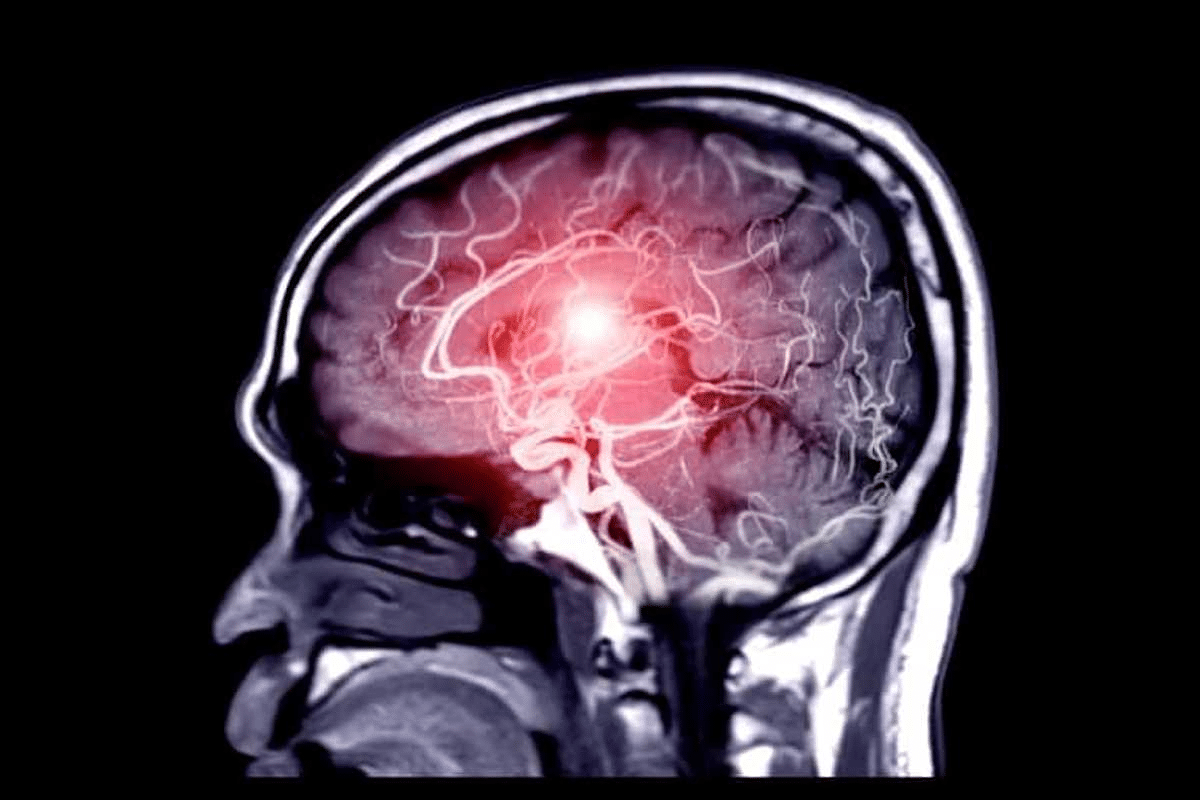

Advances in Neuroimaging

New neuroimaging methods are helping us diagnose Alzheimer’s before it’s too late. PET scans with special tracers show where beta amyloid plaques are in the brain. MRI scans show brain structure and can spot signs of Alzheimer’s.

Neuroimaging is not just for diagnosis. It also helps track how the disease progresses and if treatments work. As these tools get better, they’ll be even more vital in fighting Alzheimer’s.